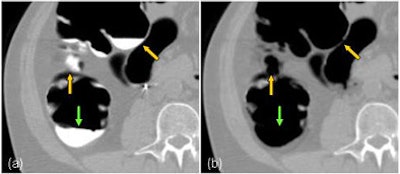

| Illustration of the artifact of degradation of the soft-tissue structures in electronic cleansing method. A thin haustral fold [arrow in (a)] submerged in the tagged materials was erroneously removed after the application of a thresholding-based electronic cleansing method [arrow in (b)]. A small polyp [arrow in (c)] submerged in the tagged materials was erroneously removed by the electronic cleansing method [arrow in (d)]. |